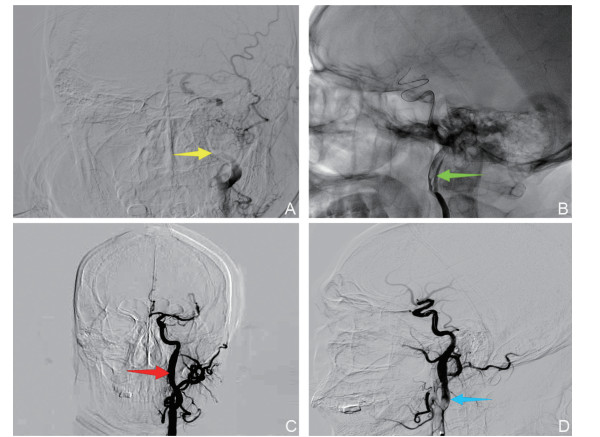

• The clinical diagnosis and management of acute cerebral infarction resulting from carotid artery dissection remain a topic of debate. A patient with acute cerebral infarction caused by carotid artery dissection was initially treated with intravenous thrombolysis using alteplase (0.9 mg/kg). Due to inadequate clinical improvement, bridging endovascular therapy (stent placement in the left internal carotid artery) was performed, resulting in complete clinical resolution. The National Institutes of Health stroke scale (NIHSS) score improved from 18 at admission to 0 upon discharge. At the 3-month follow-up, no new clinical symptoms were observed in the patient. Based on data from 52 patients with acute cerebral infarction caused by carotid artery dissection reported in PubMed, Wanfang, and CNKI.com between 2010 and 2024, it is suggested that endovascular therapy (such as stent implantation or anti-thrombolysis) may be employed for the timely management of vascular occlusion resulting from dissection in order to achieve favorable outcomes.